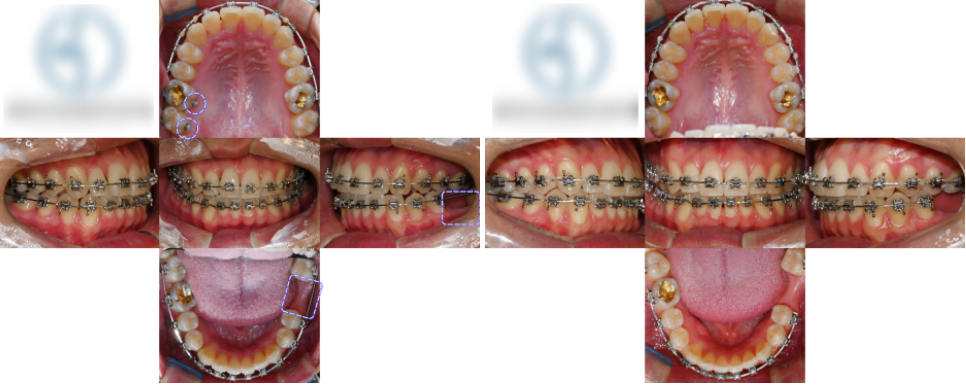

촬영일 : 23.12.04

촬영일 : 23.12.04

촬영일 : 23.12.04

구강 내를 살펴보니,

오른쪽 측절치가 반대 교합 상태였고,

왼쪽 아래 어금니(#36)는

머리 부분이 깨져 치근만 남아 있었습니다.

촬영일 : 23.12.04

치열은 덧니가 심하고 어금니 파절 부위는

시간이 지나며 인접치가 쓰러져

임플란트 를 심기엔 충분하지 않은 공간이

될 수 있기에 공간을 유지해야 됩니다.

촬영일 : 24.04.25

우선 남아있는 치근만 남은 어금니(#36)는

발치 후 치유 기간을 거쳤고,

그 사이 인접 치아들이 공간 쪽으로

쓰러지는 것을 예방하기 위해

공간 유지를 진행했습니다.

촬영일 : 24.04.25

이후 브라켓과 와이어를 이용해

인접치를 서서히 이동시킵니다.

촬영일 : 24.09.10/ 25.01.03

덧니를 해소하고 정중선을 맞추는 동시에,

임플란트 를 식립할 수 있도록

공간을 유지합니다.

촬영일 : 25.04.02

시간이 지나며 치열이 가지런해지고,

웃을 때 입술 비대칭도 점차 완화되었습니다.

촬영일 : 25.04.02

교정 종료 시점에서는

어금니 부위에 임플란트 를 심어진 모습입니다.

촬영일 : 23.12.04/ 25.04.02

앞니 배열도 가지런히 정렬되었으며,

위아래 교합도 정상적인 관계를 형성되었습니다.